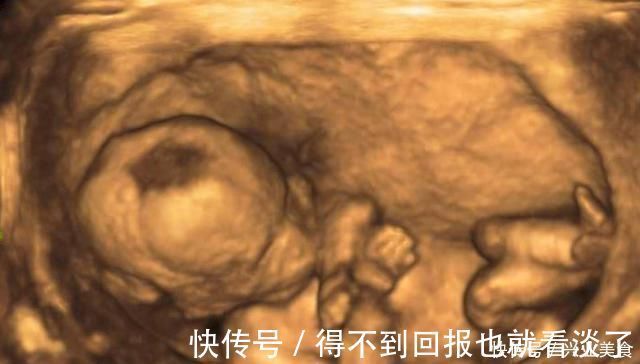

怀孕期间,尤其是宝宝不断长大之后,一般会去医院做四维彩超检查。这个时候从四维彩超检查上可以看到宝宝的相貌,甚至是一些身体的细节。我们都知道去医院做检查的时候,医生不会直接向你透露宝宝的性别,但是孕妈可以细心观察,或许从这几件事上就能够看出宝宝的性别了。

做四维彩超检查的时候是允许家属陪同的,这个时候家属医生也愿意和家属以及孕妇来分享一下宝宝的相貌。所以在聊天的过程中,孕妈不妨多多观察一下四维彩超,因为医生一不小心可能就会照到宝宝的隐私部位,这个时候孕妈或许就能够知道宝宝的性别了。

而且很多孕妈在去医院做四维彩超检查的时候,会要求把四维彩超的结果刻成光盘。一般来说,医院会懒得去剪辑四维彩超的结果,所以整个过程都会被录到光盘里面,这个时候回到家里之后,孕妈不妨多看几遍光盘,或许从宝宝四维彩超的过程中就能够判断出来宝宝的性别。

其实除了通过四维彩超的过程,做了四维彩超的检查单上可能也有你想知道的答案。所以孕妈不妨通过四维彩超检查单上的数据来判断一下,比如说可以通过孕囊的长度来判断一下。